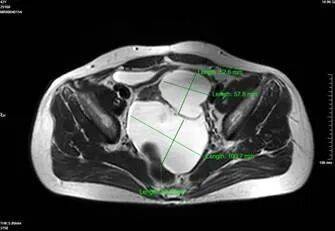

2. 影像学进一步检查:若超声无法明确,可做盆腔CT或MRI。CT/MRI能更清晰地显示假囊的位置、大小、与周围器官的关系,排除恶性病变(如卵巢癌、转移性肿瘤等)。